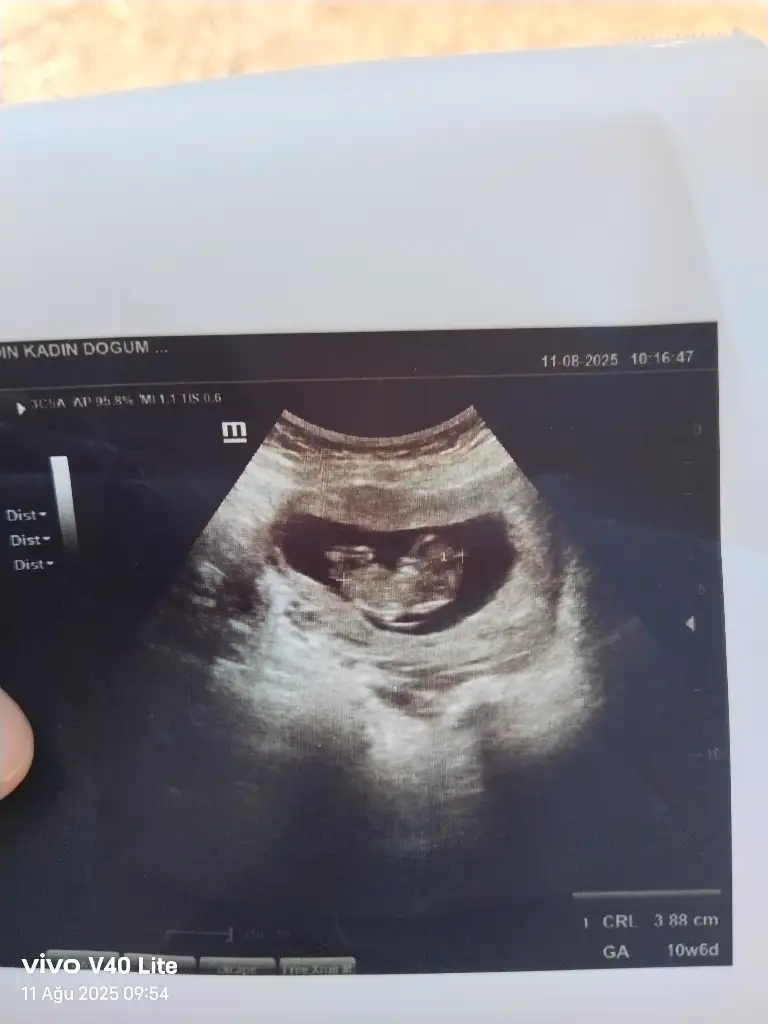

Merhaba benimde yorumlarmisiniz rica etsem 11+1Bariz erkek görüyorum, sağlıcakla gelsin inşallah![]()

Sizce benim nedir 11+1Erkek bence

Kesesini erkeğe benzettim sağlıkla gelsinSizce benim nedir 11+1

TeşekkürlerKesesini erkeğe benzettim sağlıkla gelsin![]()